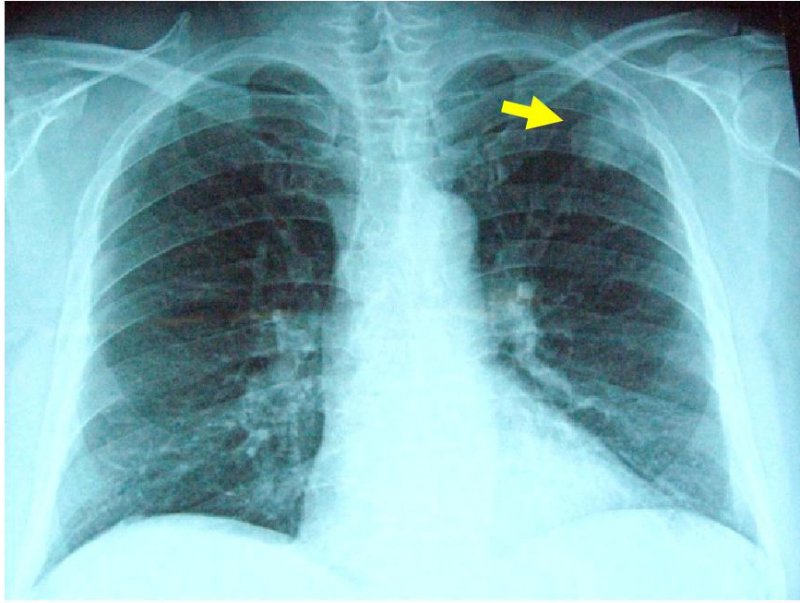

肺癌その進行度により病期IからIV期に分類されます。また、肺癌は非小細胞肺癌(腺癌、扁平上皮癌、大細胞癌、腺扁平上皮癌、腺様嚢胞癌、粘表皮癌など)と小細胞肺癌に分類することができます。どの病期または組織型にあてはまるかにより治療法は異なります。非小細胞肺癌の場合、I期、II期、IIIA期の一部であれば手術療法の適応となります。なかでもI期症例は胸腔鏡手術の良い適応とされています。当科では癌の進展状況、全身状態、心肺機能など十分考慮した上で、手術可能であるか、術式をどうするか(胸腔鏡下手術の適応など)さらには術後補助化学療法を行うかを呼吸器内科医と連携をとりながら肺癌を治療していきます。また、当科は胸腔鏡手術いわゆる内視鏡手術を積極的に行い、患者さんの体に優しい手術を得意としています。当院で施行した胸腔鏡下右肺葉切除術+縦隔リンパ節郭清の術後の創部の写真を以下に示します。まず、5cm大の小開胸創のみの胸腔鏡手術で、患者さん側に対して侵襲が小さく、創部痛も極めて最小限に抑えます(Single Incision Thoracoscopic surgery:SITS写真1)。さらに、胸腔内の状況に応じて3つないし4つのポート孔から手術を行う(いわゆる完全胸腔鏡手術:Pure Video Assisited Thoracoscopic surgery:Pure VATS写真2)または、小開胸創(5から 10cmサイズ)と1つないし2つのポート孔から行う手術(Video Assisted Thoracoscopic Surgey:VATS写真3)を行います。当科での胸腔鏡手術は1)手術の大部分がモニター下で、2)小開胸創のサイズは5から10cm(術者の手が胸腔内に挿入不能なサイズ)、3)肋骨切除がなされない手術と定義しています。胸腔鏡下手術とは胸腔鏡(カメラと光源を兼ね備えた器具)を用いて視野を確保し、胸腔鏡や自動縫合器、鉗子などを挿入し、手術を行う手術法です。呼吸器外科での胸腔鏡手術の厳密な定義はいまだ定めれてはいませんが、当科では患者さんに対して上記の術式で最大限低侵襲になるよう心掛けております。また、進行癌に対しても限りなく完全切除(腫瘍を完全に切除すること)を目指して手術を行います。

左肺癌の画像所見

胸部XP(左上肺野に腫瘤影あり)

胸部CT